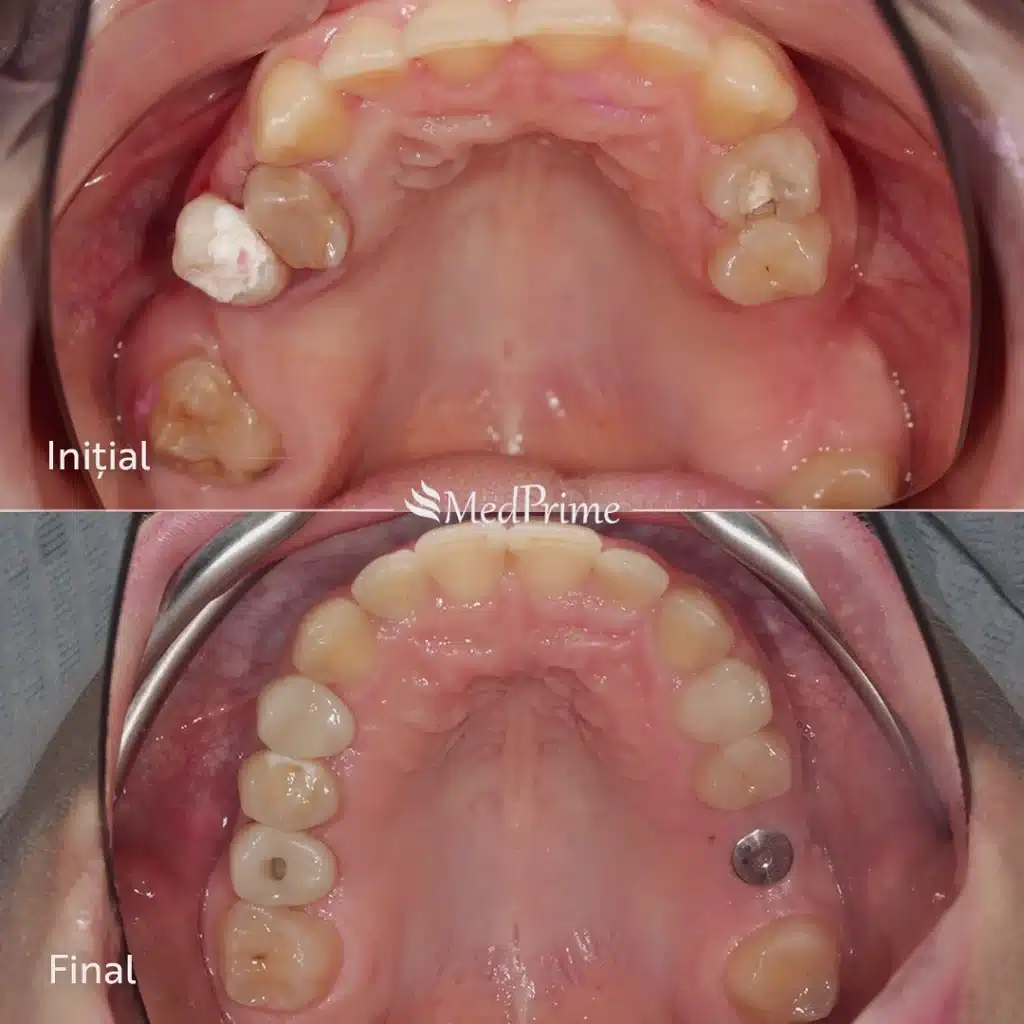

Mai jos prezentăm un caz real de implant dentar All‑on‑4 / All‑on‑6 realizat în clinica MedPrime din Cluj. Radiografiile înainte și după intervenție arată stabilizarea imediată, poziția corectă a implanturilor și reconstrucția completă a arcadelor.

Intervenția All‑on‑4 / All‑on‑6 permite înlocuirea completă a dinților lipsă printr‑un protocol rapid și minim invaziv. Implanturile sunt poziționate strategic pentru a asigura stabilitate ridicată, iar pacienții beneficiază de restaurări imediate și rezultate estetice excelente.

Acest caz a fost realizat la MedPrime Cluj.